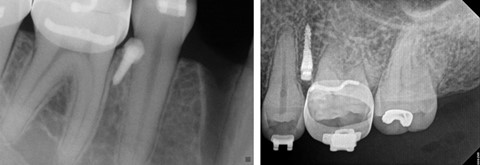

Another applications of orthodontic mini implants is to intrude super erupted teeth. The use of temporary anchorage devices for molar intrusion might be done with sectional braces. It is recommended to place two infinity mini implants; in the buccal 8.5 mm long and in the palatal 11 mm to compensate for the thickness of palatal tissue.